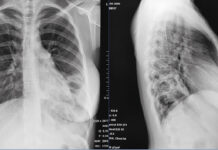

CAZ DE TBC LA MINULESCU

O elevă de la Colegiul Național ”Ion Minulescu” a fost depistată cu TBC. Aceasta este internată la unitatea medicală din Scornicești, iar colegii și...